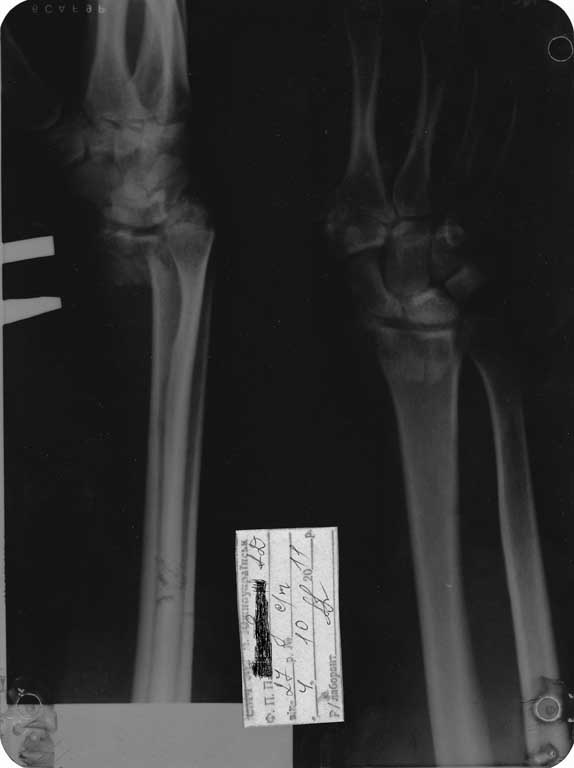

Скорей всего у Вашего пациента перелоп Barton-а

Порекомендую волярный срединный доступ (осторожно выделите n.medianus!), oстеосинтез АО малой 3,5мм Т-образной волярной пластиной, если есть locking plate - еще лучше! Pри ушивании - ни в коем случае не сшивать карпальную поперечную связку!- будет компрессионная нейропатия n.medianus !

Неплохо было бы выставить информацию о возрасте? А так доступ волярный, фиксатор любой из DVR.

Переломы волярной пластины (ладонные) со смещением относится к нестабильным переломам и удержать подвывих кисти можно только волярной (Butress) пластиной. Одной из первых пластин для лечения дистальных переломов луча

является DVR Hand Innovation (сегодня DePuy)

Сегодня все компании: Synthes, Stryker, Zimmer, Acumed, TriMed и т.д. имеют пластины для фиксации дистального перелома лучевой кости. На снимке метод фиксации дистальных переломов, справа Stryker, а слева пластина Synthes,

женщина 58 лет, политравма.